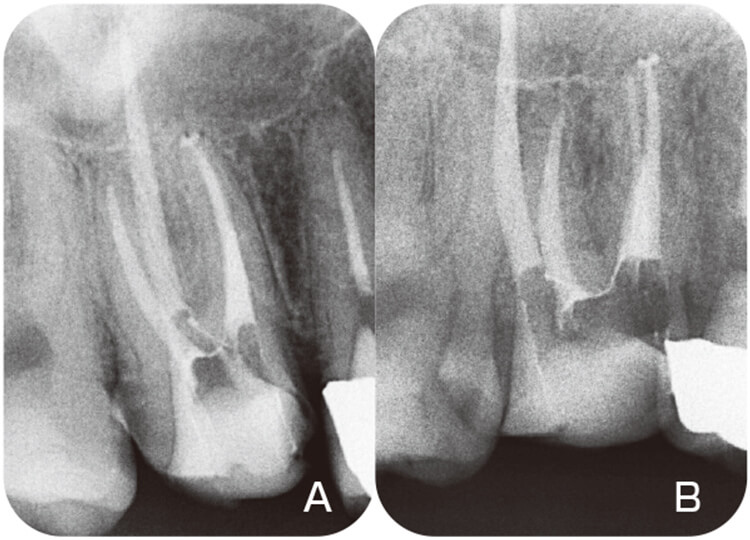

破折ファイル(図12)がある時はその周囲象牙質を削除しながら除去を試みる。根管壁の薄いところは避けながら、下顎大臼歯であれば破折ファイルの頰側と舌側を中心にチップを使用する。破折ファイルの食い込みをはずすことができればファイルは根管口の方に浮き上がってくる(図13)。除去後にはデンタルX線写真で確認する(図14)。破折ファイルに直接超音波振動を加えると、二次破折を引き起こすことがあるので注意が必要である。

図12 58歳女性の再根管治療。下顎右側第一大臼歯遠心舌側根管に折れ込まれたファイル。超音波用エンドファイルダブルを使用して除去を試みた。

図13 根管口に飛び出してきたファイル。この破折ファイルを根管から取り出せばよい。

図14 術前(A)とファイル除去後(B)のデンタルX線写真。ファイル除去操作による根管拡大はほとんどなかった。